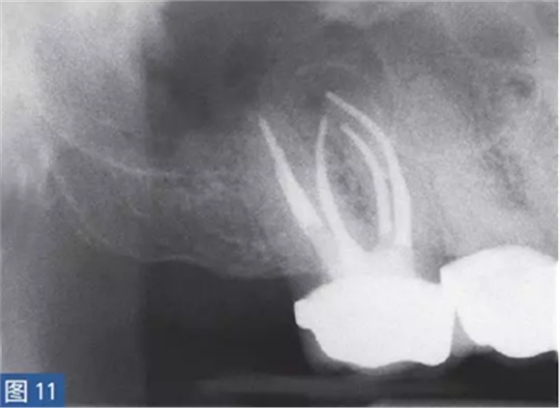

慢性根尖周膿腫(圖10 和11)是由長(zhǎng)期持續(xù)的炎癥引起的。膿液穿通骨和口腔黏膜,并通過(guò)口腔黏膜或上皮的瘺管流出。這些通到表皮的瘺管通常可能作為皮膚損傷而被錯(cuò)誤處置。此外,瘺管也可能存在于牙周并通過(guò)齦溝引流。瘺管可以部分或完全地被上皮所包繞,這些上皮又被炎性結(jié)締組織包圍。

臨床診斷顯示牙髓電活力測(cè)試結(jié)果為陰性。除非瘺管閉合,否則叩診和觸診通常都不會(huì)引起疼痛。放射學(xué)檢查,根尖周組織表現(xiàn)從無(wú)變化到發(fā)生明顯變化。

圖10:17 牙齒CAA。術(shù)前放射學(xué)檢查,利用牙膠尖顯示瘺管?;颊咭?7 牙齒局部瘺管而前來(lái)就診,訴無(wú)特殊臨床癥狀。

圖11: 17 牙齒CAA。根管治療12 個(gè)月后。